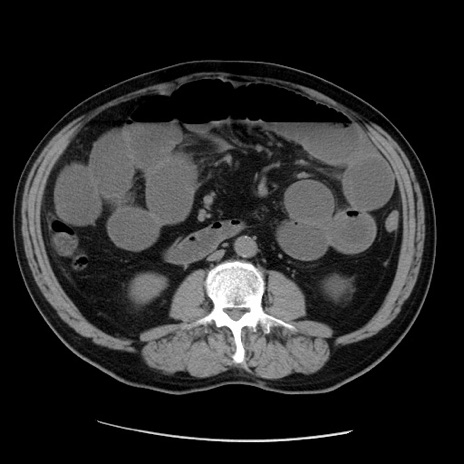

症例20(横断像)

【症例】 60歳代男性

【主訴】 腹部膨満、嘔吐

【現病歴】5日前頃より倦怠感を認め食事量減少し4日前の朝嘔吐、食事摂取困難となった。 3日前近医受診し点滴施行され整腸剤などを処方された。 当日他院を受診し、腹部膨満著明、炎症反応の上昇(CRP10.8、WBC11200)あり、紹介受診となる。

【身体所見】 意識JCS1 受け答えがはっきりしないBP 111/57mHg、 P 67bpm、、BT35.2°C、SpO2 97%(RA)、 腹部:膨隆、打診で鼓音あり、全体的に圧痛有り、腸蠕動音(-)、反跳痛ははっきりせず。

【データ】WBC 11400、CRP 14.20